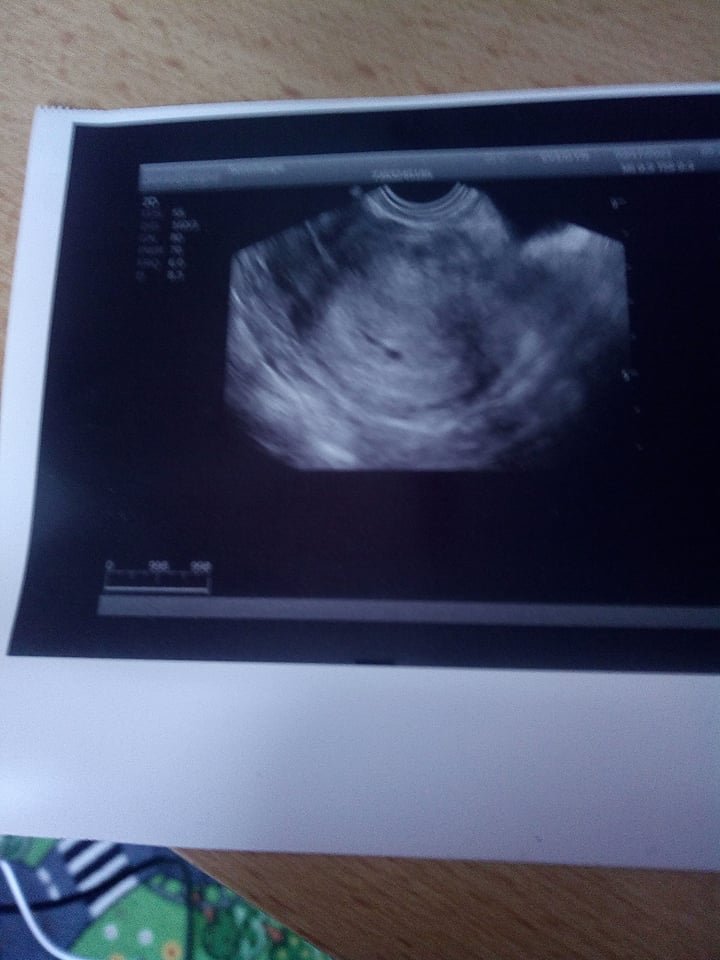

@chesekhake tak to mě moc mrzí ☹ a jak jsi poznala,že ti praskl?jako kdyby to i my odešlo,bolelo by to,ale mám doma 4 krásné chlapečky,tak ti by mi to vynahradili a do pátého bych šla až za 6 let 😀 a měla jsi ho nad miminkem?nebo kde?ta tečka je váček a to dlouhé nad tím je hematom.